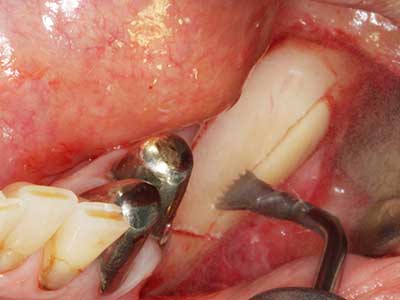

Bei der Knochenblockentnahme zeigen sich weitere Vorteile für die Piezochirurgie: Neben der bereits beschriebenen hohen Präzision bei der Osteotomie stellt sich gerade die Verwendung der dünnen Sägespitzen als besonders materialschonend heraus. Bei der Verwendung insbesondere von Lindemannfräsen sind mit deutlich höheren Entnahmeverlusten durch die dickere Instrumentenspitze zu rechnen (Lakshmiganthan, Gokulanathan et al. 2012). Die insbesondere bei retromolar entnommenen Blocktransplantaten notwendige basale Abtrennung wird durch speziell hierfür vorgesehene rechtwinklige Sägen erleichtert, so dass die Piezochirurgie als präzises, übersichtliches und sicheres Verfahren zur retromolaren Knochenblockgewinnung angesehen wird (Happe 2007) (Abb. 1-12).

Indikation: Nervnahe Präparation

Wie bereits erwähnt lassen sich auch im Bereich der chirurgischen Zahnerhaltung Indikationsgebiete für die Piezochirurgie finden. Durch die Verwendung von speziellen Arbeitsspitzen wird die Darstellung der Wurzelspitze erleichtert, und gerade im unteren Prämolaren- und oberen Seitenzahnbereich lassen sich Nerven und Kieferhöhlenschleimhäute einfacher schützen. Bei undichtem apikalen Abschluss präparieren abgewinkelte Diamantspitzen zielgenau die Resektionskavität für das retrograde Wurzelfüllmaterial. Die Spitzen können durch die Ultraschalltechnik sehr grazil gestaltet sein, was Übersicht und Größe der Zugangskavität verbessert. So gehört in dieser Indikation die Anwendung der Ultraschallchirurgie zu den Standardverfahren der Wurzelspitzensresektion (Del Fabbro, Tsesis et al. 2010, Scarano, Artese et al. 2012).